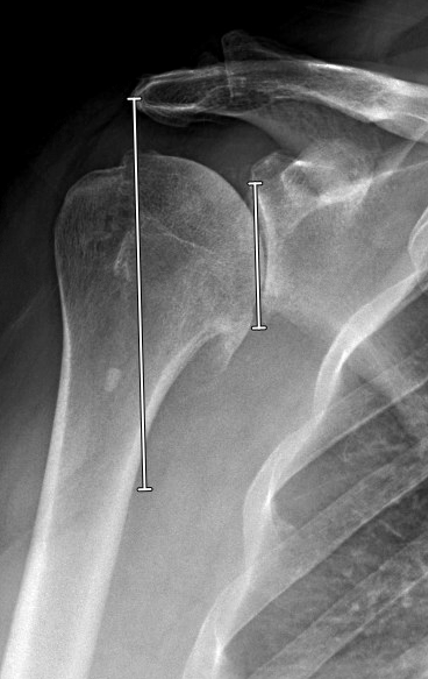

The PACS (Picture Archiving and Communication System) is available to most shoulder surgeon. It has tools for “trying” different prosthetic head sizes as shown below.

Using angle tool at 135º relative to the humeral shaft, the PACS tools can then be used to explore the location of the head cut for this size head component, including its relation to the cuff insertion superiorly and to the osteophytes inferiorly.

Based on this head cut, the thickness of the humeral head implant can be estimated measuring the distance from the medial aspect of the circle to the cut line. This example shows a 20 mm thickness head component.